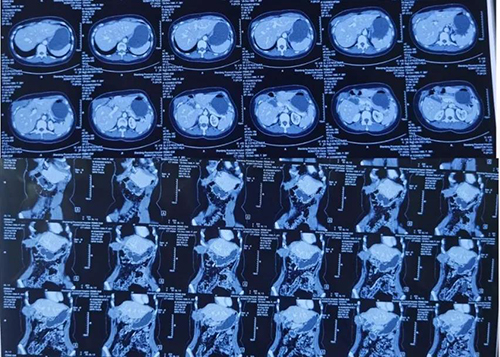

患者为青年女性,2014年3月于外院行肿物切除术,2015年及2016年分别与外院行肿物切除+肋骨部分切除术及射频消融术等多次治疗。日前出现肿瘤复发并到省立医院胃肠外科就诊。

石玉龙以及各科室专家团队共同为患者实施了手术。该患者肿瘤位置跨越膈肌,累及胸壁腹壁,术中探查发现其侵犯多个脏器。结合术中情况,专家团队密切配合、联手施治,为患者进行了胸腹壁肿物切除以及结肠、胃、肝、肺等器官并肋骨的部分切除。联合胸腹壁及多脏器切除后,患者缺损极大,修补困难,专家给予胸廓重建、补片修补及带蒂背阔肌筋膜瓣转移术。整台手术历经8个多小时的紧张操作,最终获得成功,治疗效果极佳,目前患者已恢复出院。